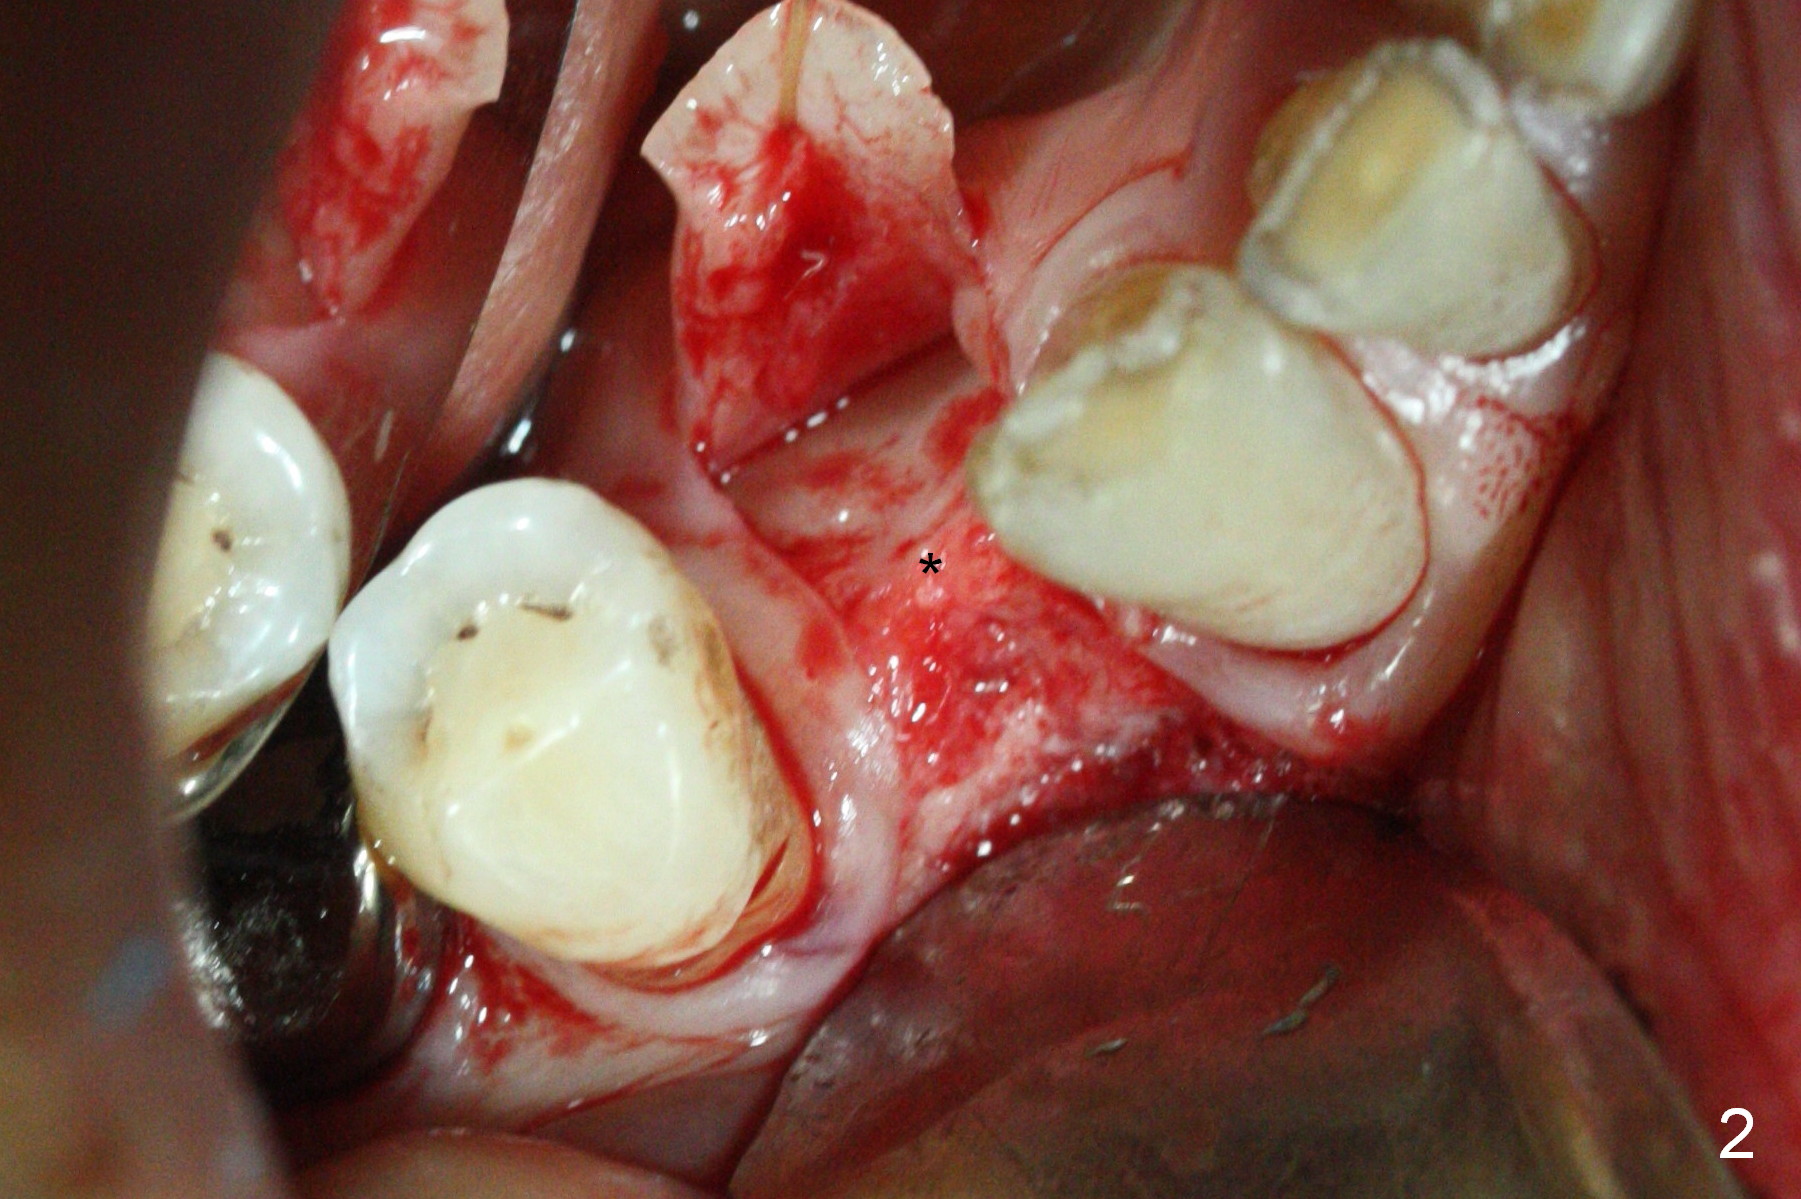

In fact the mesiodistal space of the site of #28 is within normal limit. The buccal plate atrophy is striking (Fig.1) with a fistula (^, associated with underlying residual root tip). When the flaps are raised, the ridge is triangular with the lingual plate (Fig.2 *) higher than the buccal one. Because of the slope, the multiple-drill approach is adopted in stead of single-drill one, because the marking bur is wobbling after 1.6 mm osteotomy at 13 mm (Fig.3). After placement of a 4x11 mm implant, a 4.5x4(2) mm abutment is inserted (Fig.4). The abutment and the implant act as a mesh (framework) so that bone graft and collagen membrane can be laid upon them buccolingually. When the flaps are sutured, there is less tension than that without the abutment. Furthermore, the buccal tissue volume seems to be increased (Fig.5 (<: fistula, which should heal soon), as compared to Fig.1). Tale photos to show effectiveness of the simultaneous GBR and disappearance of the fistula. Three months postop (Fig.6,7 (incomplete abutment seating)), the implant is loaded for intrusion of the opposing supraerupted tooth. The patient returns with chief complaint of food impaction between #27 and 28 three years 7 months post cementation; there is an open contact. Before pick up impression the distal convex surface of #27 is trimmed. The repaired crown has tight proximal contacts before (Fig.9,10) and after (Fig.11) retightening and cementation.